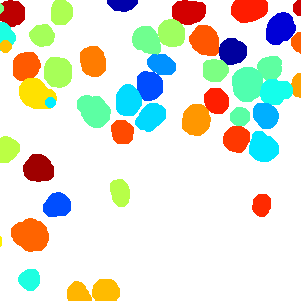

As an essential part of digital pathology, histopathology image analysis is playing increasingly important role in cancer diagnosis, which can provide direct and reliable evidence to diagnose the grade and type of cancer. This paper deals with nuclei segmentation, an important step in histopathological image analysis. The purpose of nuclei semgentation is not only counting the number of nuclei but also obtaining the detailed information of each nucleus. So unlike nuclei detection, here the outputs are the contour of each nucleus instead of only the position of their central points. Hence we can exactly extract each nucleus from the image and make it available for further analysis. For example, the features of the individual nucleus and the distribution of nuclei clusters can be used to grade and classify status of breast cancers [3, 4]. Because of appearance variation such as color, shape, and texture, nuclei segmentation from histopathological images could be very challenging, as illustrated in Fig.1, in which it is very challenging even for human to recognize and segment all nuclei within the images. Fig.1(a) and Fig.1(b) illustrate two histopathological images from different organs. Fig.1(c) and Fig.1(d) are two histopathological images from same organ but have different cancer grade.

Figure 6 shows how our method segments the nuclei step by step. The color variety is well controlled by the color normalization procedure. The prediction result shows clear nuclear areas and nucleus boundaries. In the final segmentation result and ground truth image, each nucleus is represented by a different color.